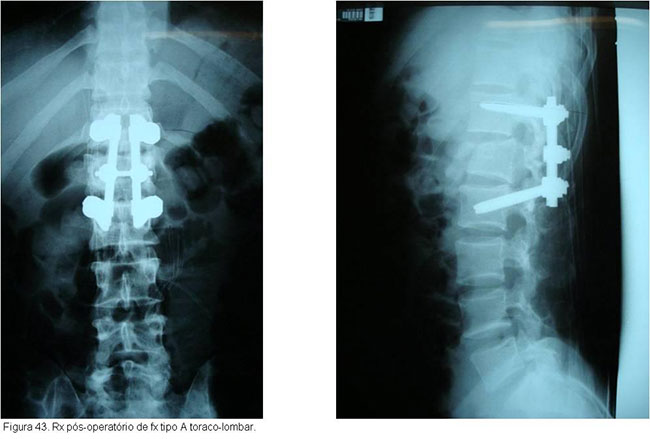

O tratamento seguirá o mesmo raciocínio discutido anteriormente, dependendo de quais estruturas estiverem lesadas. Particularidades da região toraco-lombar e lombar determinarão abordagens especificas caso a caso.(figuras 40, 41, 42 3, 44, 45)